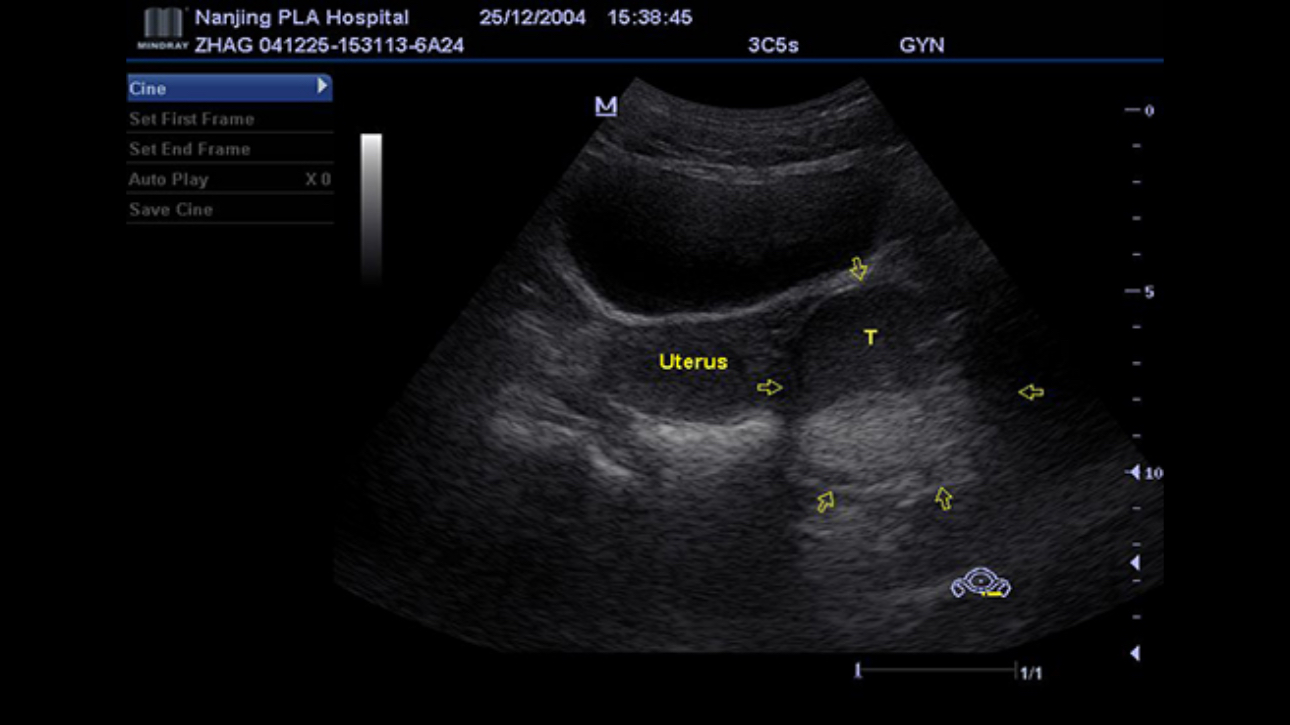

A fully-featured laptop style color Doppler system, M5 offers uncompromised 2D performance and exceptional value in a highly convenient and easy to use package. Equipped with advanced technologies such as Smart 3D TM and efficient workflow software, makes M5 ideal for use within obstetrics and gynecology application field.

Smart 3DTM

Freehand 3D fetal image rebuilding for more informative observation.